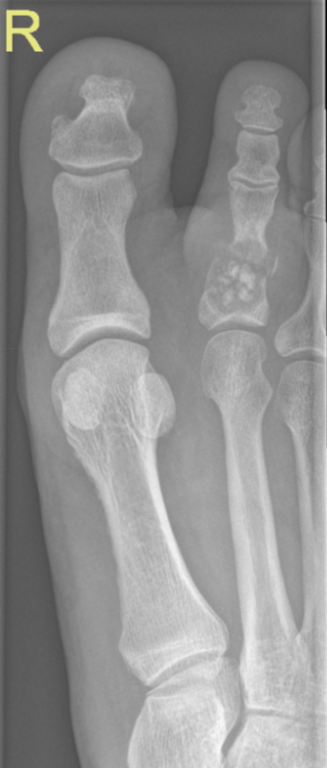

Pathological fracture through enchondroma